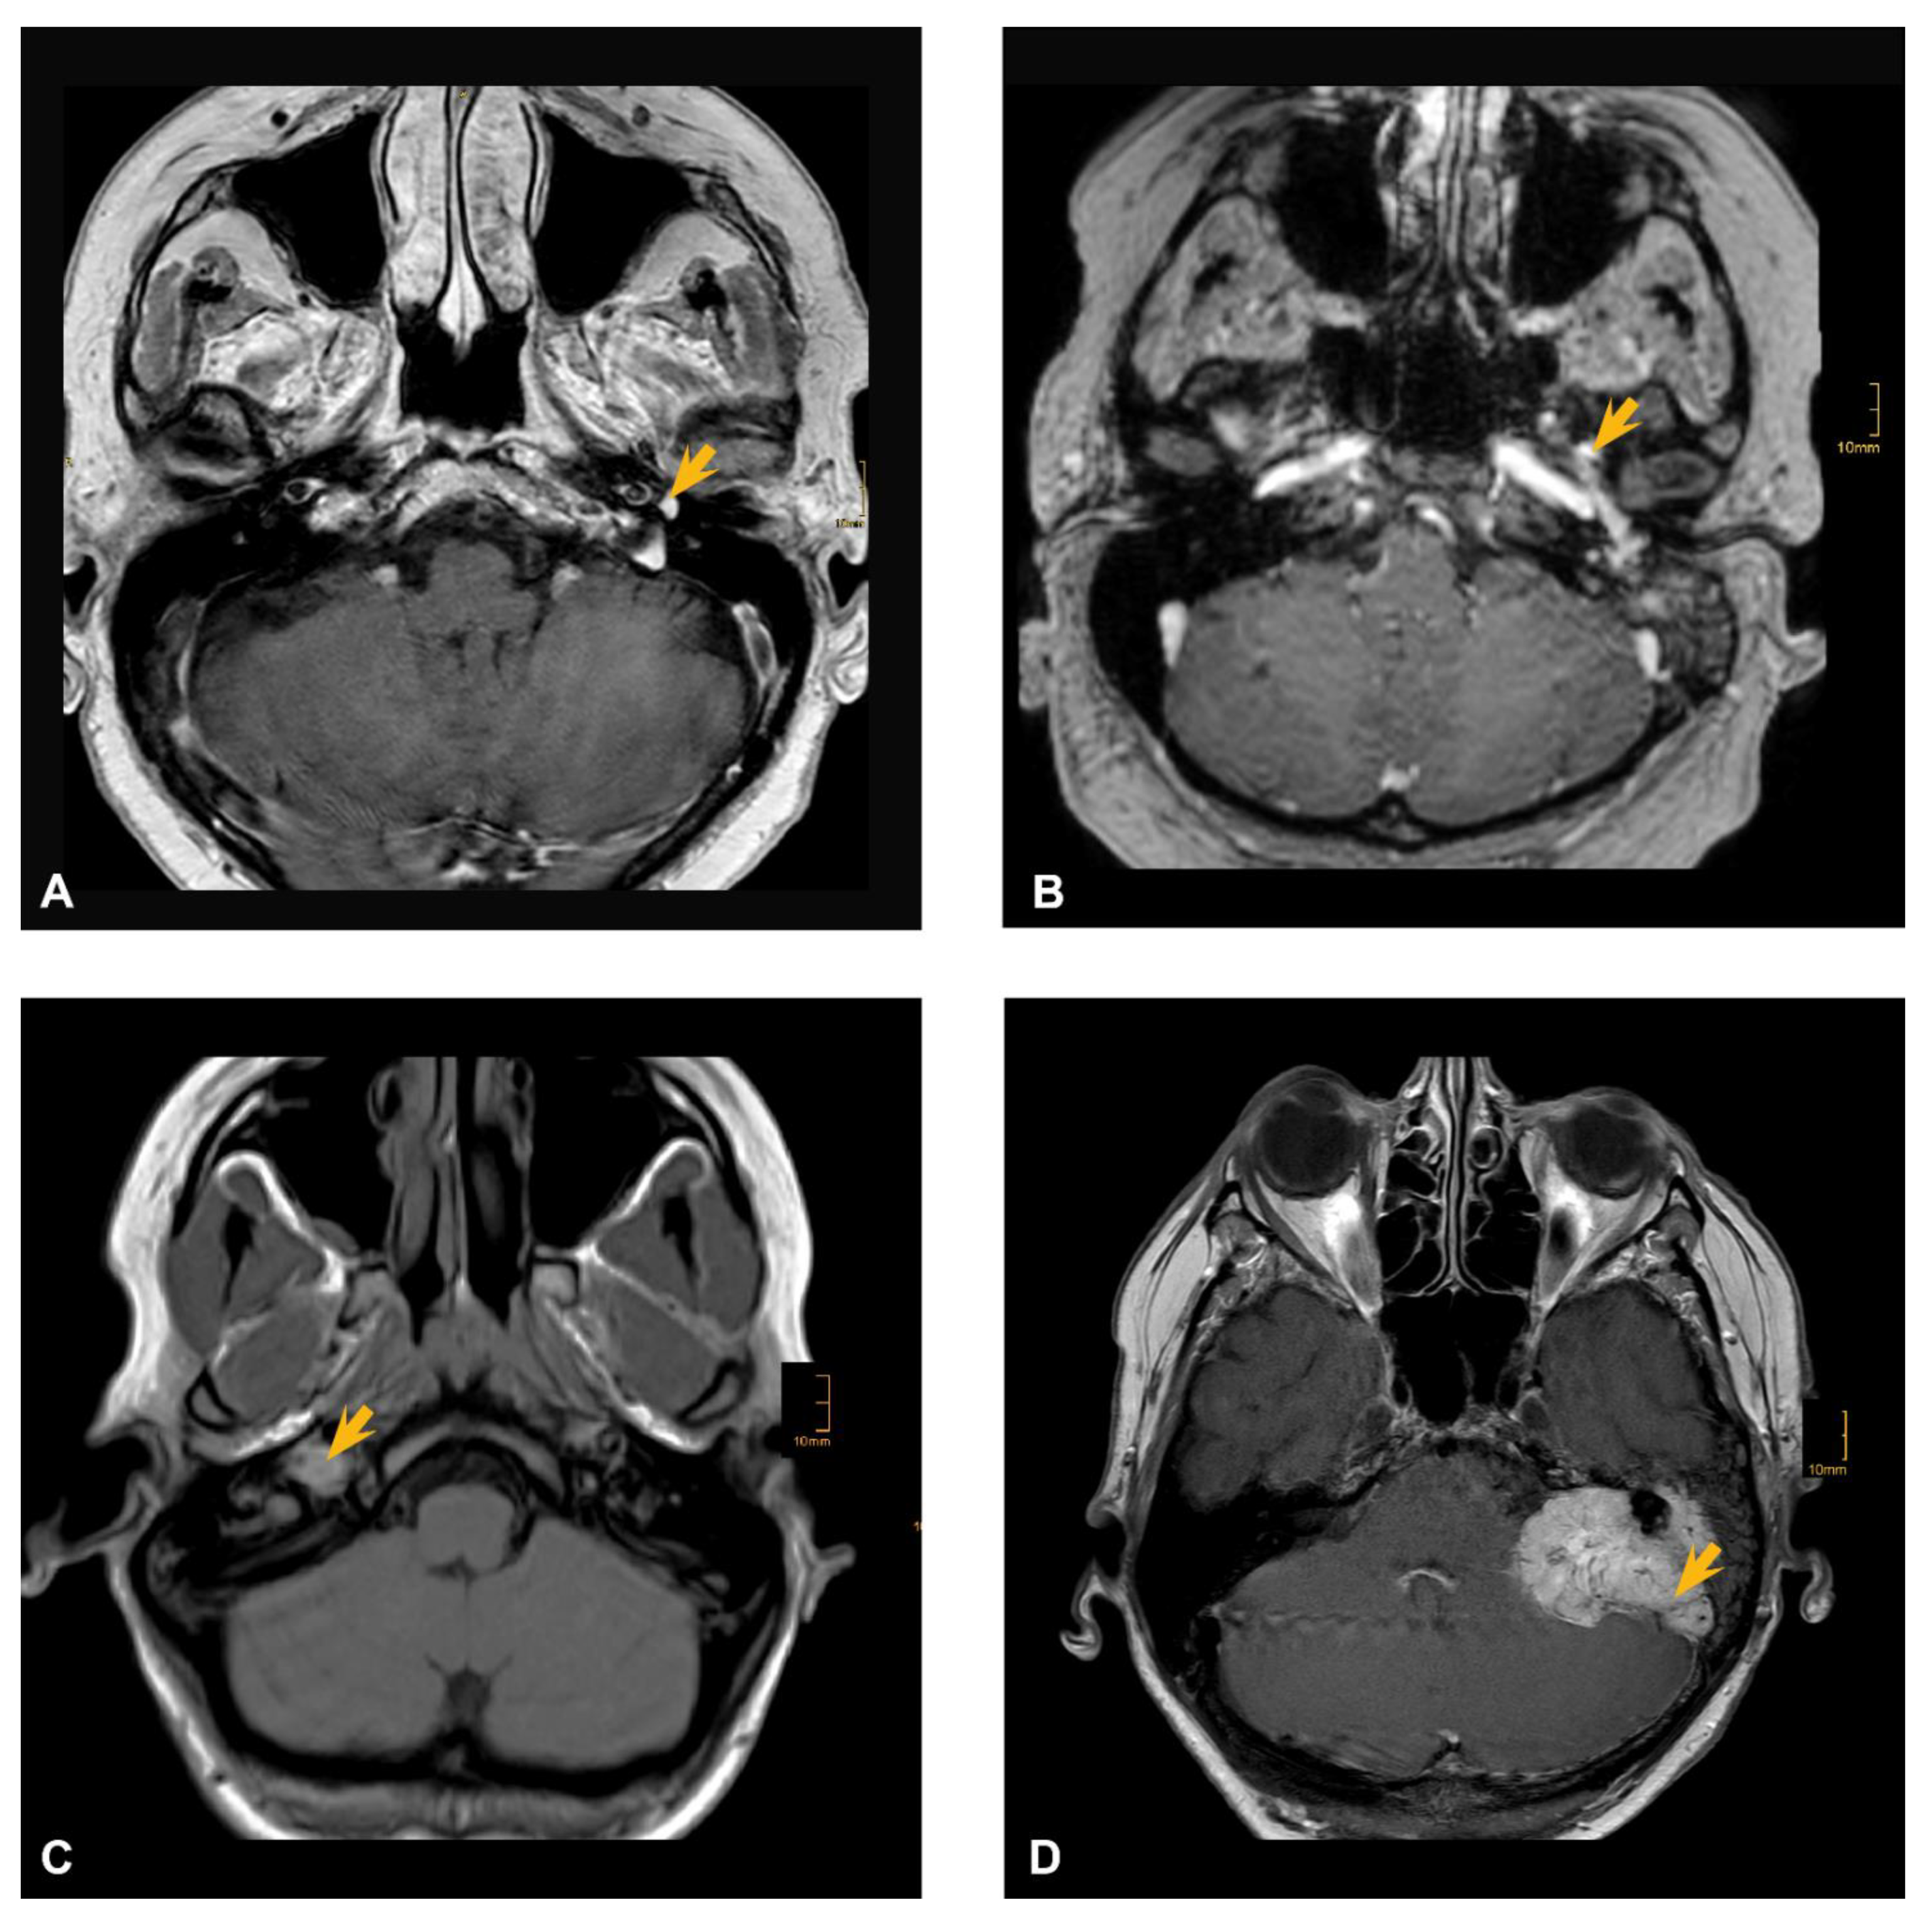

Acquired data included age, sex, date of diagnosis, tumor location, symptoms, CNP, treatment strategy, complications, clinical examination reports, pre- and postoperative CT and MRI imaging and tumor recurrence in FU. Categorization of TBPs according to the Fisch classification system [2] was performed by two experienced neuroradiologists. Figure 1 represents examples of main tumor categories (Fisch A to D) from our patient population. Histological confirmation of paraganglioma was assessed in all patients.

Figure 1. MRI examples of Fisch grades (AD) in the respective population. (A) cranial MRI scan of Fisch A1 TBP, (B) cranial MRI scan of Fisch B3, (C) cranial MRI scan of Fisch C1, (D) cranial MRI scan of Fisch De2. The yellow arrow indicates tumor location in each radiological scan.